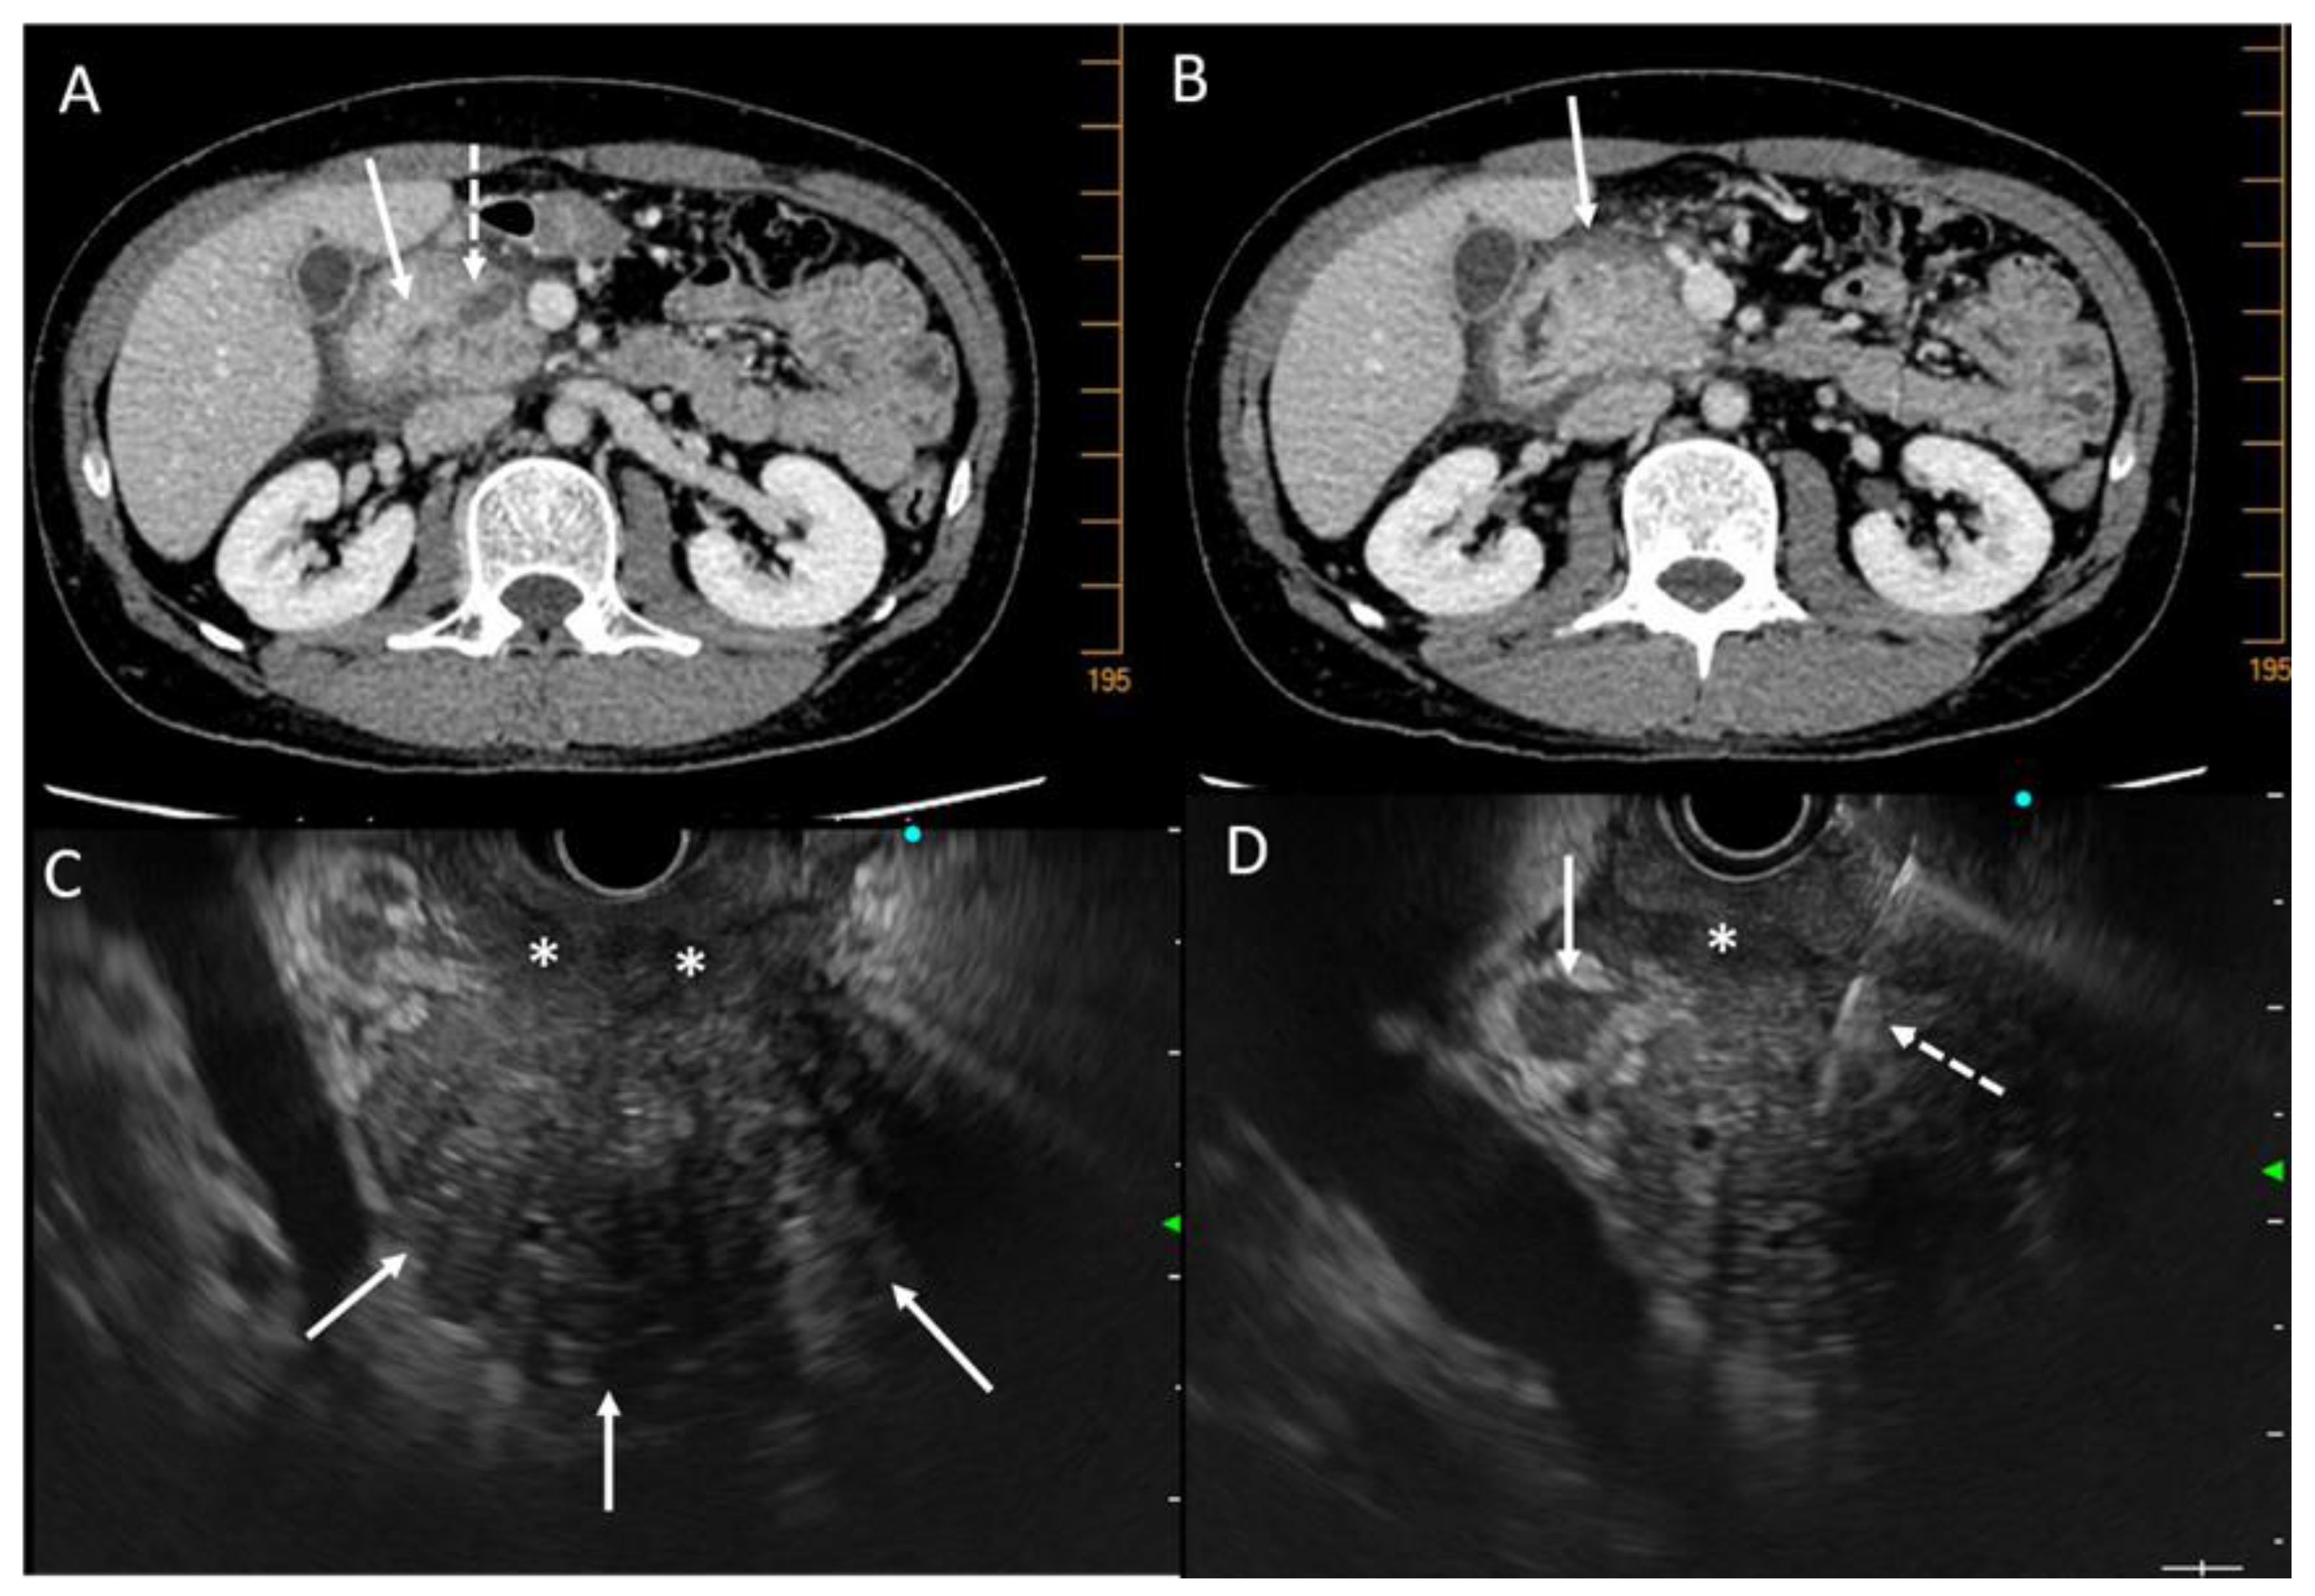

| Signs Evocative of Benign Disease | Signs Evocative of Malignant Disease | |

|---|---|---|

| Parenchymal signs | Pseudotumorous CP and IPMN:

|

Paraduodenal pancreatitis:

| ||

AIP:

| Duct signs | Obstructive CP and IPMN:

| Vessels signs | Pseudotumorous CP:

| Other signs | AIP: